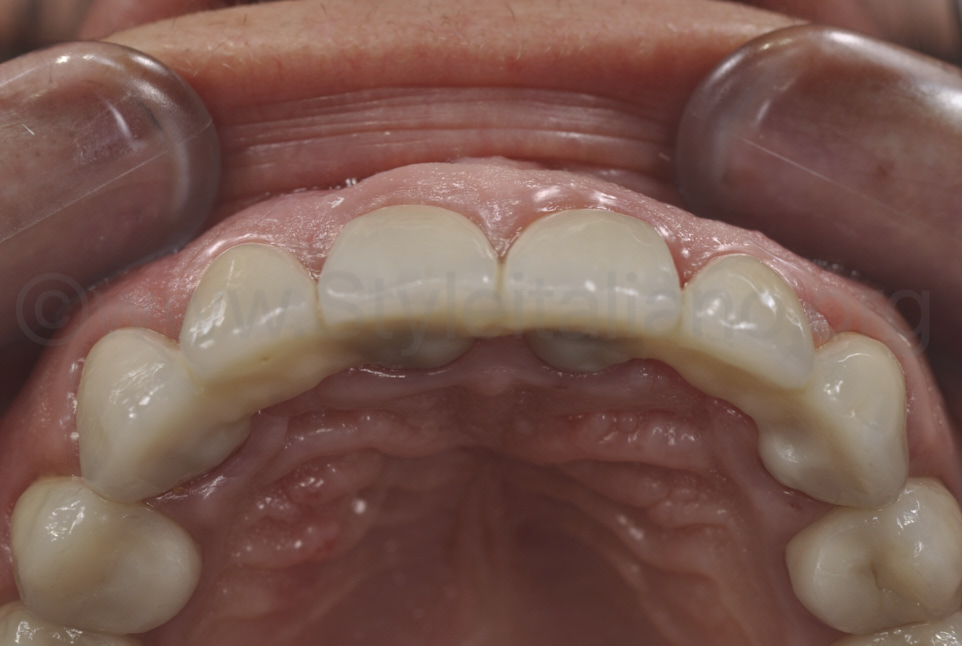

Фото 17.

Вигляд оклюзії з однаково опуклими твердими та м’якими тканинами.